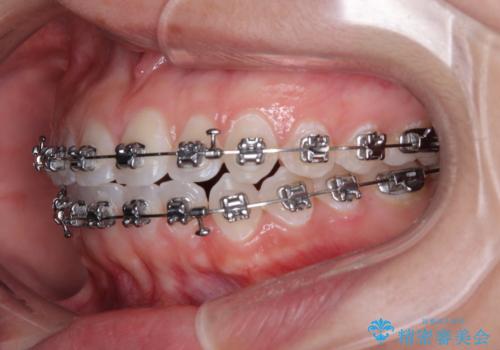

【モニター】マウスピース矯正が煩わしい ワイヤー装置での非抜歯矯正

- 矯正装置

- メタルブラケット

- 上下前歯のデコボコを気にして来院された患者様です。

ワイヤー矯正でもマウスピース矯正でも可能でしたが、短期間で、自身の手を煩わせることなく治療を行いたいとのことで、ワイヤー装置にて矯正治療を行うこととしました。

僅か半年強、あっという間に治療を終えることができました。